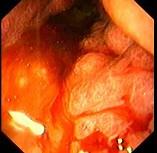

问题 男性患者,45岁,平素身体健康,近2个月出现上腹饱胀不适,偶有隐痛,伴纳差,近2天有黑粪,胃镜如图。关于本病,下列说法正确的有 ( )

选项 A.可诊断为胃癌 B.可诊断为胃间质瘤 C.处于早期 D.处于进展期 E.应马上手术治疗

答案 ADE